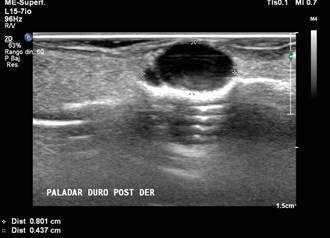

Al examen intraoral era desdentada total superior y parcial inferior, con múltiples lesiones cariosas y portadora de prótesis. A nivel palatino presentaba nódulo en límite de paladar duro-blando hacia la derecha, próximo a línea media, redondeado, azul, superficie lisa, fluctuante, 5 mm de diámetro, indoloro, con un tiempo de evolución desconocido (Figura 3). Se realizó ecografía de paladar por sospecha de malformación vascular, que concluye lesión de aspecto quístico en el sector posterior derecho de paladar duro, con contenido denso (Figura 4).

Las presentaciones clínicas reportadas en la literatura comparten con nuestros casos la apariencia nodular y superficie lisa. Respecto a la consistencia, existe variabilidad en nuestros casos, el primero tenía una consistencia firme, lo que llevó a plantear la hipótesis de adenoma pleomorfo, mientras que el segundo caso presentaba consistencia fluctuante y coloración azulada, simulando una malformación vascular o un carcinoma mucoepidermoide11. En dichos casos, muchas veces la ecotomografía aporta valiosa información diagnóstica, dada sus bien conocidas ventajas12, especialmente en el estudio de lesiones pequeñas y superficiales con transductor lineal de alta frecuencia, en donde otros métodos de diagnóstico por imágenes presentan grandes limitaciones, especialmente en cuanto a artefactos, resolución espacial y de contraste13. En el caso 2 se solicitó un estudio por ultrasonografía, para descartar una posible lesión vascular y permitió orientarnos hacia un tumor de glándula salival.